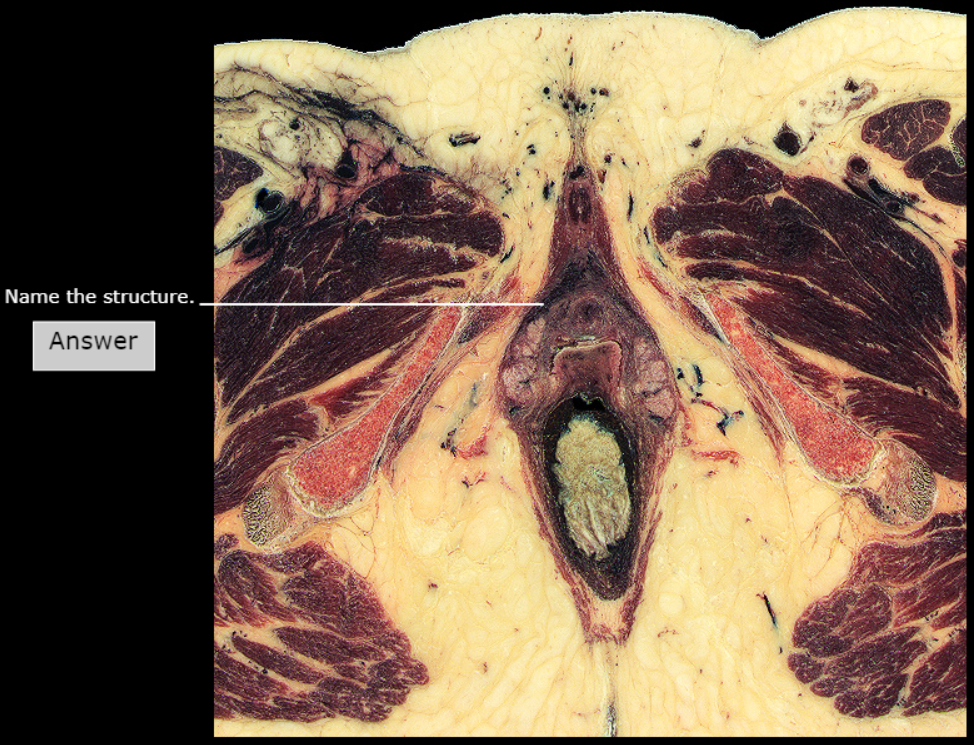

Vaginal orifice

Labia Minora

Bulb of vestibule

Glans of clitoris

Crus of Clitoris